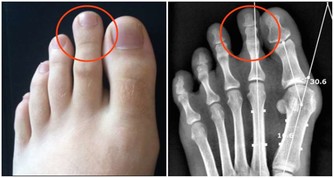

牙結石粗糙的表面又可以吸附更多的細菌,細菌產生毒力因子,進而刺激牙周組織發生炎症。當牙齦處於炎症狀態時,毛細血管會擴張充血,一旦受到刺激(如刷牙、進食等),牙齦就會出血,嚴重時甚至可能出現自發性出血。